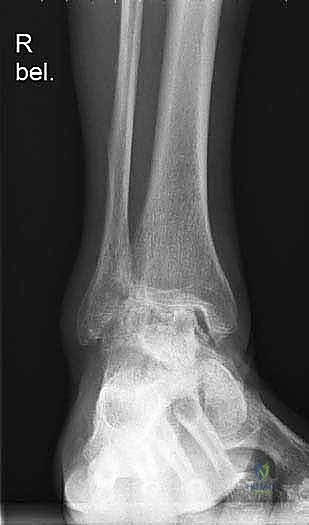

لفهم أهمية جراحة استبدال الكاحل، يجب أولاً فهم تشريح هذا المفصل المعقد. يتكون مفصل الكاحل من التقاء ثلاث عظام رئيسية:

1. عظمة الظنبوب (Tibia): وهي عظمة الساق الكبرى التي تشمل الجزء الداخلي والعلوي من الكاحل.

2. عظمة الشظية (Fibula): وهي عظمة الساق الصغرى التي تشكل الجزء الخارجي من الكاحل.

3. عظمة الكاحل (Talus): وهي العظمة السفلية التي ترتكز عليها عظام الساق وتعمل كمفصلة للحركة.

تُغطى نهايات هذه العظام بطبقة ناعمة ومرنة تسمى الغضروف المفصلي، والذي يعمل كوسادة لامتصاص الصدمات وتقليل الاحتكاك أثناء الحركة. عندما يتآكل هذا الغضروف، تبدأ العظام بالاحتكاك ببعضها البعض، مما يسبب ألماً مبرحاً وتورماً وتيبساً.

1. التقييم والتحضير قبل الجراحة

يتم إجراء فحوصات شاملة تشمل الأشعة السينية (X-rays)، والأشعة المقطعية (CT scan) لإنشاء نموذج ثلاثي الأبعاد لكاحل المريض. يساعد هذا د. هطيف في اختيار الحجم الدقيق للمفصل الصناعي وتحديد زوايا القطع بدقة متناهية.